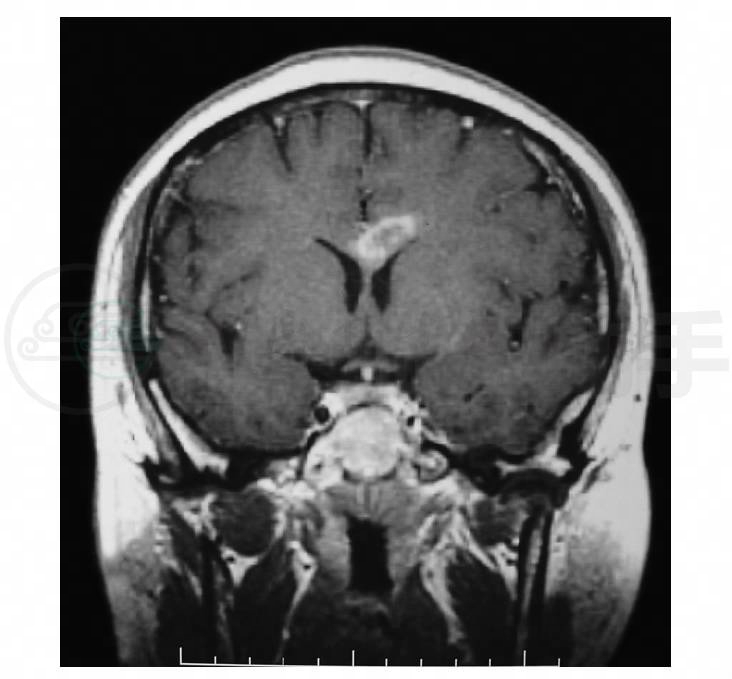

7.头部MRI(2006-5-30)示胼胝体膝部及体部可见不规则T1WI低信号T2WI高信号片状影,大小约4. 1cm×2. 0cm×1. 5cm,增强扫描呈轻度强化(图1~图3)。头颅增强MRI(2006-6-7)示病灶明显强化(图4,图5)。

图5 头颅MRI冠状位T1WI增强扫描示病灶轻度强化